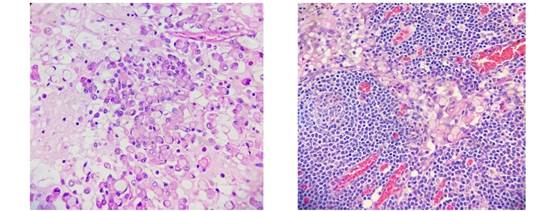

Se tomaron biopsias de la estenosis que informaron infiltración de la mucosa gástrica antral por adenocarcinoma moderada a pobremente diferenciado, ulcerado, con presencia de células en anillo de sello. Se realizó gastrectomía parcial con anastomosis Billroth II y linfadenectomía sin complicaciones (Figura 1 y 2).

Figura 1: Carcinoma gástrico con abundantes células anillo de sello

La macroscopía de la pieza reportó lesión vegetante y ulcerada, estenosante, Borman III de 8 x 5 cm, que ocluía 100% de la luz y comprometía todo el espesor parietal. La microscopía reportó carcinoma pobremente diferenciado con células en anillo de sello. Se estudiaron 8 ganglios linfáticos y todos fueron positivos. Se catalogó como T3N3M0.